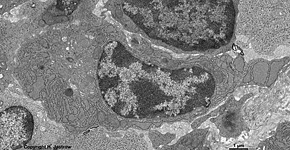

Zellkern eines

Lymphocyten (Ratte)

Das Kernplasma (Karyoplasma, Karyolymphe, Terminologia histologica: Nucleoplasma; englisch nucleoplasm) stellt den Inhalt der Zellkerne dar. Es besteht hauptsächlich aus Wasser und erscheint lichtmikroskopisch im ungefärbten Präparat homogen mit stellenweisen dunkleren Verdichtungen. Bei letzteren handelt es sich um Kernkörperchen (Nukleoli) oder Chromatingranula. Nach Fixierung und Färbung von Geweben verhält sich das Karyoplasma aufgrund des darin enthaltenen Chromatins basophil. Oft wird das Kernplasma stärker angefärbt als das Zytoplasma. Durch Ausfällung und Verklumpung von feinen Cromosomenfibrillen, die auch als Chromatin bezeichnet werden, lassen sich dann feinste Fäden und größere Brocken erkennen, die Chromozentren.

Die Dichte des im Karyoplasma gelegenen Chromatins hängt von der Aktivität der Zelle ab. Das Chromatin (Terminologia histologica: Chromatinum, englisch: chromatin) besteht aus Nucleoproteinen, Desoxyribonucleinsäure (DNS; englisch: desoxyribonucleic acid = DNA), Histonproteinen und Nicht-Histonproteinen sowie Zentromeren (Verknüpfungsbereiche der Arme von Chromosomen; Terminologia histologica: Centromerus; englisch: centromere). Innerhalb des Chromatins unterscheidet man hellere Regionen mit lockerem Chromatin (Euchromatin; Terminologia histologica: Euchromatinum, englisch: euchromatin) und dunklere, elektronendichtere Bereiche mit verklumptem Chromatin (Heterochromatin; Terminologia histologica: Heterochromatinum, englisch: heterochromatin). Schon lichtmikroskopisch, besonders aber im Elektronenmikroskop lassen sich im Karyoplasma das helle Euchromatin und das elektronendichtere, also dunklere Heterochromatin gut unterscheiden. Dabei gehen die Bereiche ineinander über, d.h. während längere Bereiche nicht genutzter DNS in einem Heterochromatinklümpchen an Histonproteine zusammengeballt liegen, sind funktionsrelevante Abschnitte derselben DNS im daneben liegenden Euchromatin zu finden. Dieses ist bei genauer Betrachtung auch nicht ganz homogen und wird unter Euchromatin genau beschrieben.